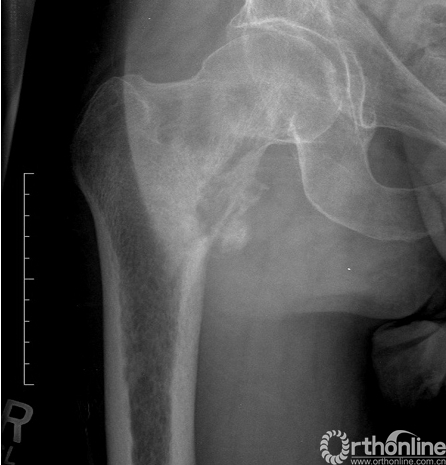

影像学特点:佩吉特病有典型的X线表现,粗大的骨小梁,增厚的骨皮质及病变骨直径的增大(图11)。疾病的进展典型的表现为先溶骨性改变后发展为成骨性改变,但大部分是混杂在一起同时进行的。在脊柱侧位片上,椎体四面的骨皮质增厚形成“相框”样外观改变。负重的下肢骨骼,特别是胫骨,在长期病变过程中可能导致弯曲畸形(图12)。

图11. 骨盆佩吉特病,骨盆和股骨近端弥漫性受累,表现为骨小梁粗大,坐骨直径增加(短箭头)和皮质增厚(长箭头)。